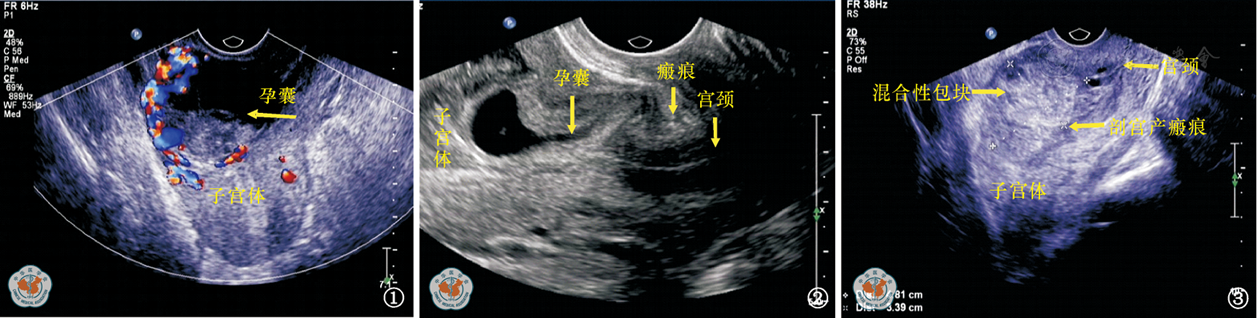

图3 剖宫产瘢痕妊娠包块型 超声检查提示,子宫前壁下段瘢痕处混合性包块,4.8 cm×3.4 cm大小